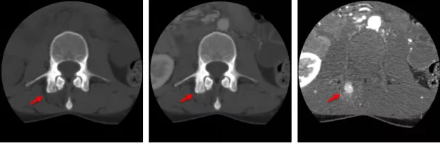

骨智能柔性減影成像功能發(fā)現隱匿骨占位病灶